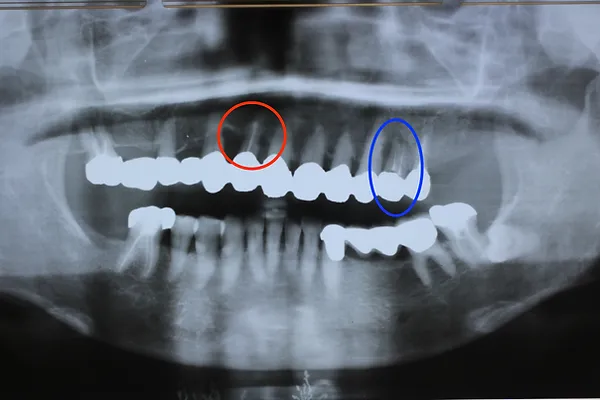

6入れ歯にしないブリッジ治療【ケース3】

このケースの患者さんは上の歯の歯槽膿漏が心配で来院されました。上の歯は11本残っており、下の写真の緑色に囲われた歯を1本抜歯して、計10本の歯を使って端から端まで繋げる治療を行いました。H22.5月に治療が始まり、H23.1月に完成しました。

H22.5のレントゲン

H31.2月には下の写真の青色に囲われた歯が根の先の病気でダメになり抜歯をすることになりましたが、歯の見えている部分はそのままで根だけを切って抜歯しました。そのため1本歯が少なくなり、9本で端から端まで繋がっています。

H31.2のレントゲン

下のレントゲン写真はR3.12月に撮影した写真ですが、赤丸の歯槽膿漏の歯は1枚目のH22.5月の頃からほとんど変化しておらず、13年経っても大丈夫です。全部の歯が繋がっていて、1本1本の歯の動きがないため、長く維持できています。

R3.12のレントゲン

以下の写真はR4.9月に撮影した写真です。

2022年現在72歳の女性の方です。

治療が終了してから13年経過していますが、今も大丈夫です。